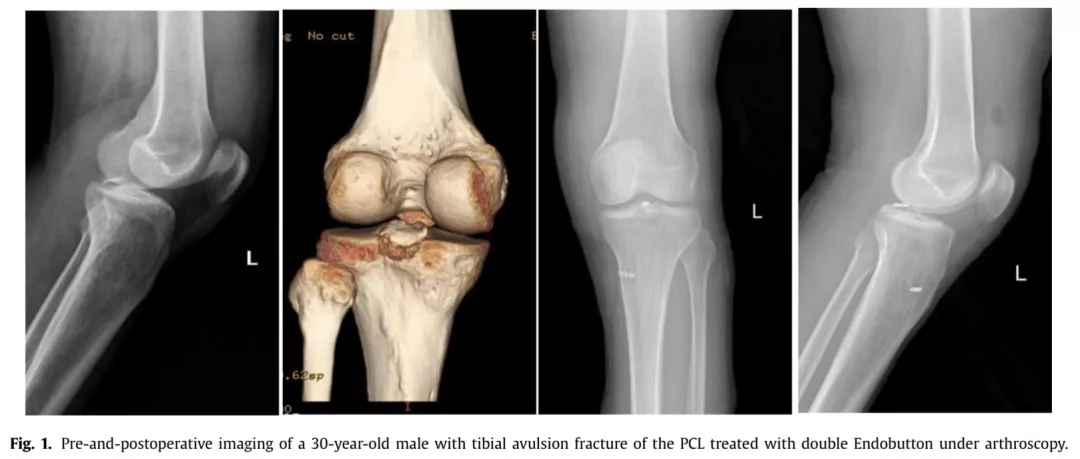

不会关节镜,如何用钢板固定胫骨后叉止点骨折?

胫骨后叉止点骨折可分为三型,I型为无移位骨折,通常可保守治疗,对II型和III型移位骨折,通常采取手术治疗,以恢复膝关节稳定性。 关节镜下Endobutton固定后叉止点骨折因其微创、固定有效等优点,已成为治疗的首选。但关节镜手术技术要求高,因此,有学者采用自制钩钢板切开复位固定后叉止点骨折,取得了良好效果。结果发表在2021.07 Injury期刊上。